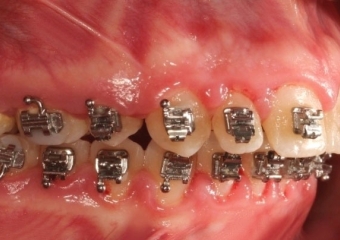

Mordida inicial